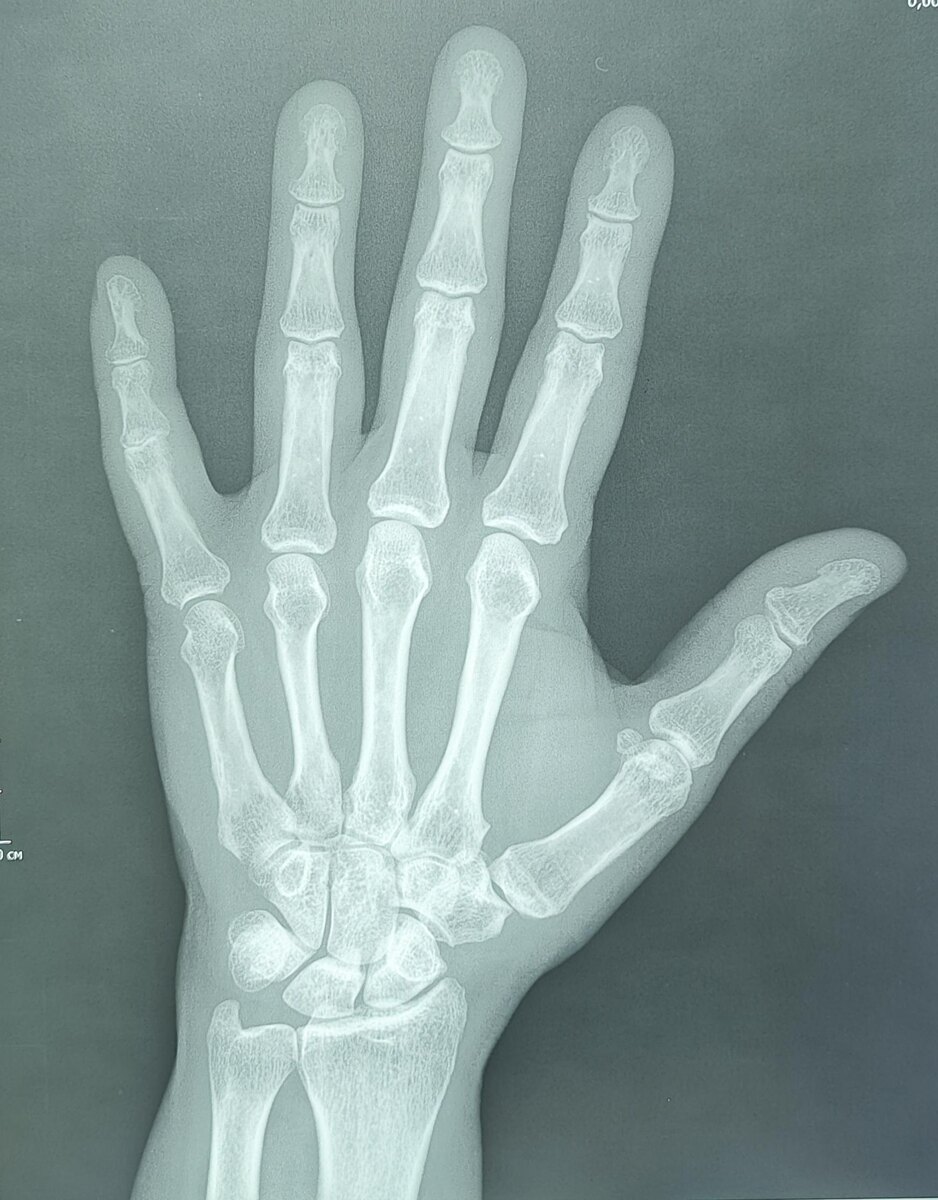

Эностоз, или костный островок, представляет собой доброкачественное образование в костной ткани, которое обычно обнаруживается случайно при рентгенологическом исследовании.

-Компактный костный островок(эностоз) дистальной фаланги пятого пальца правой кисти.

Основные рентгенологические признаки эностоза включают:

1. Очаговое затемнение:

На рентгенограмме эностоз выглядит как четко очерченный очаг повышенной плотности (гиперденсивный) в костной ткани.

2. Форма и контуры:

Образование обычно имеет округлую или овальную форму.

Контуры четкие, ровные, иногда могут быть слегка лучистыми или неровными, но без признаков агрессивного роста.

3. Локализация:

Эностоз может встречаться в любой кости, но чаще всего обнаруживается в губчатом веществе костей (например, в позвонках, тазовых костях, ребрах, длинных трубчатых костях).

4. Размер:

Размеры эностоза обычно небольшие (от нескольких миллиметров до 1-2 см), но могут варьироваться.

5. Отсутствие деструкции окружающих тканей:

Эностоз не вызывает разрушения окружающей костной ткани и не сопровождается периостальной реакцией.

6. Стабильность:

При динамическом наблюдении эностоз обычно не изменяется в размерах или растет очень медленно.

7. Связь с костными трабекулами:

Эностоз часто сливается с окружающими костными трабекулами, что создает характерный "лучистый" вид.

8. Отсутствие мягкотканного компонента:

Эностоз не сопровождается образованием мягкотканного компонента или внекостного распространения.